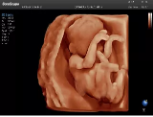

4容積探頭

積探頭是在二維圖像的基礎(chǔ)上,將連續(xù)采集的空間分布位置,經(jīng)過計算機重建算法,從而獲得完整的空間形態(tài)。

適用于:胎兒面部、脊柱和肢體等。

優(yōu)勢特點:快速獲取、掃查連續(xù)均勻、解剖結(jié)構(gòu)顯示為容積數(shù)據(jù)、準(zhǔn)確進行容積測量。